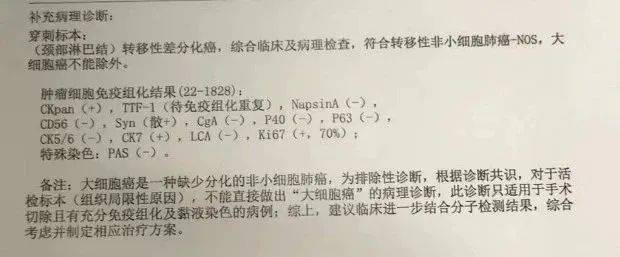

经淋巴转移灶穿刺活检,符合转移性非小细胞肺癌,大细胞肺癌不能排除,后经省医院病理会诊,会诊意见:倾向腺癌,且不支持鳞癌及神经内分泌癌,免疫组化结果 tps 约2%。

图片来源:患者提供